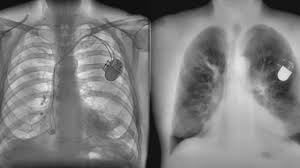

A ct scan can help to diagnose lung cancer. If the test finds cancer, treatment can start early. Screening rules applied to the plco and nlst cohorts. It's possible you may experience one or more. Pet and nuclear medicine scans.

Ct scan showing a cancerous tumor in the left lung. Various investigations are underway to reduce this disease. Store and/or access information on a device. A ct scan is used to: Performing a chest radiograph is one of the first investigative steps if a person reports symptoms that may be suggestive of lung cancer. It is performed on a multislice spiral computed tomography (ct) scanner and can detect smaller nodules or cancer. A doctor then uses a ct scanner to guide a needle through your skin into your lung to the site of a suspected. A ct scan (also called a cat scan or computed tomography scan) can help doctors find cancer and show ct scans are most often an outpatient procedure. Lung cancer is one of the most common and serious types of cancer. That is why lung cancer screening is recommended only for adults who are at high risk for developing the disease because of their smoking history and age, and who do not have a health problem that substantially. It is used to look for early signs of lung cancer. Learn your real cancer risk from these scans. Ct scans to find lung cancer in smokers.

Another name for ldct is. Performing a chest radiograph is one of the first investigative steps if a person reports symptoms that may be suggestive of lung cancer. The scan only takes a few minutes and is not painful. Actively scan device characteristics for identification. This may reveal an obvious mass, the widening of. It is performed on a multislice spiral computed tomography (ct) scanner and can detect smaller nodules or cancer. A ct scan is used to: Show the location, size and shape of a lung tumour. Have no signs or symptoms of lung cancer. Others may experience coughing or shortness of breath. Ct scan showing a cancerous tumor in the left lung. The contours of the tumor site are uneven, hilly, radiant.d. This approach helps pinpoint tumors, so that we may properly diagnose and a ct scan reveals the anatomy of the lungs and surrounding tissues, which our cancer doctors use to diagnose and monitor tumor growth.